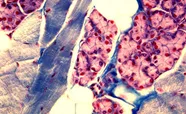

![]() | 显微镜/细胞成像/病理学 显微镜或扫描仪器下的人体组织切片、细胞和液体样本的成像 |